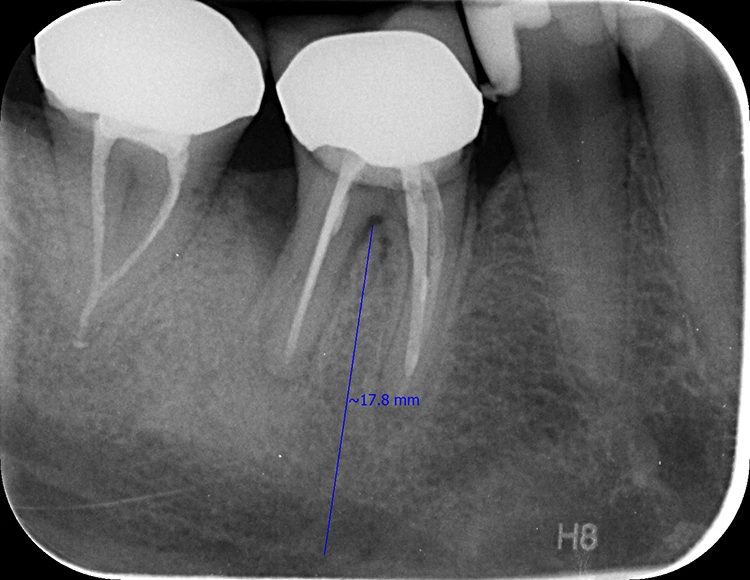

Eine Patientin (33 Jahre), Gelegenheitsraucherin (3 bis 7 Zigaretten/day) und Z.n. Thrombose im Jahr 2009, mit insgesamt unauffälliger Allgemeinanamnese kam im Juni 2020 als Schmerzpatientin in unsere Praxis. Ausgehend von Zahn 46 litt sie an einem PA-Abszess (Abb. 1).

Drei Monate nach der Extraktion des nicht erhaltungswürdigen Zahnes 46 wurde im Januar 2021 eine DVT angefertigt (Abb. 2) und es wurden Ober- und Unterkiefer abgeformt. Für die Planung der Bohrschablonen (Fremdlabor) erfolgte die Digitalisierung der Modelle mit einem Laborscanner im Eigenlabor, anschließend wurden die Daten an den Planungspartner zur Herstellung der Bohrschablonen übermittelt. Dort erfolgte die digitale Vorplanung der Implantatposition und der prothetischen Versorgung mit der Planungssoftware coDiagnostiX (dental wings) (Abb. 3 und 4).